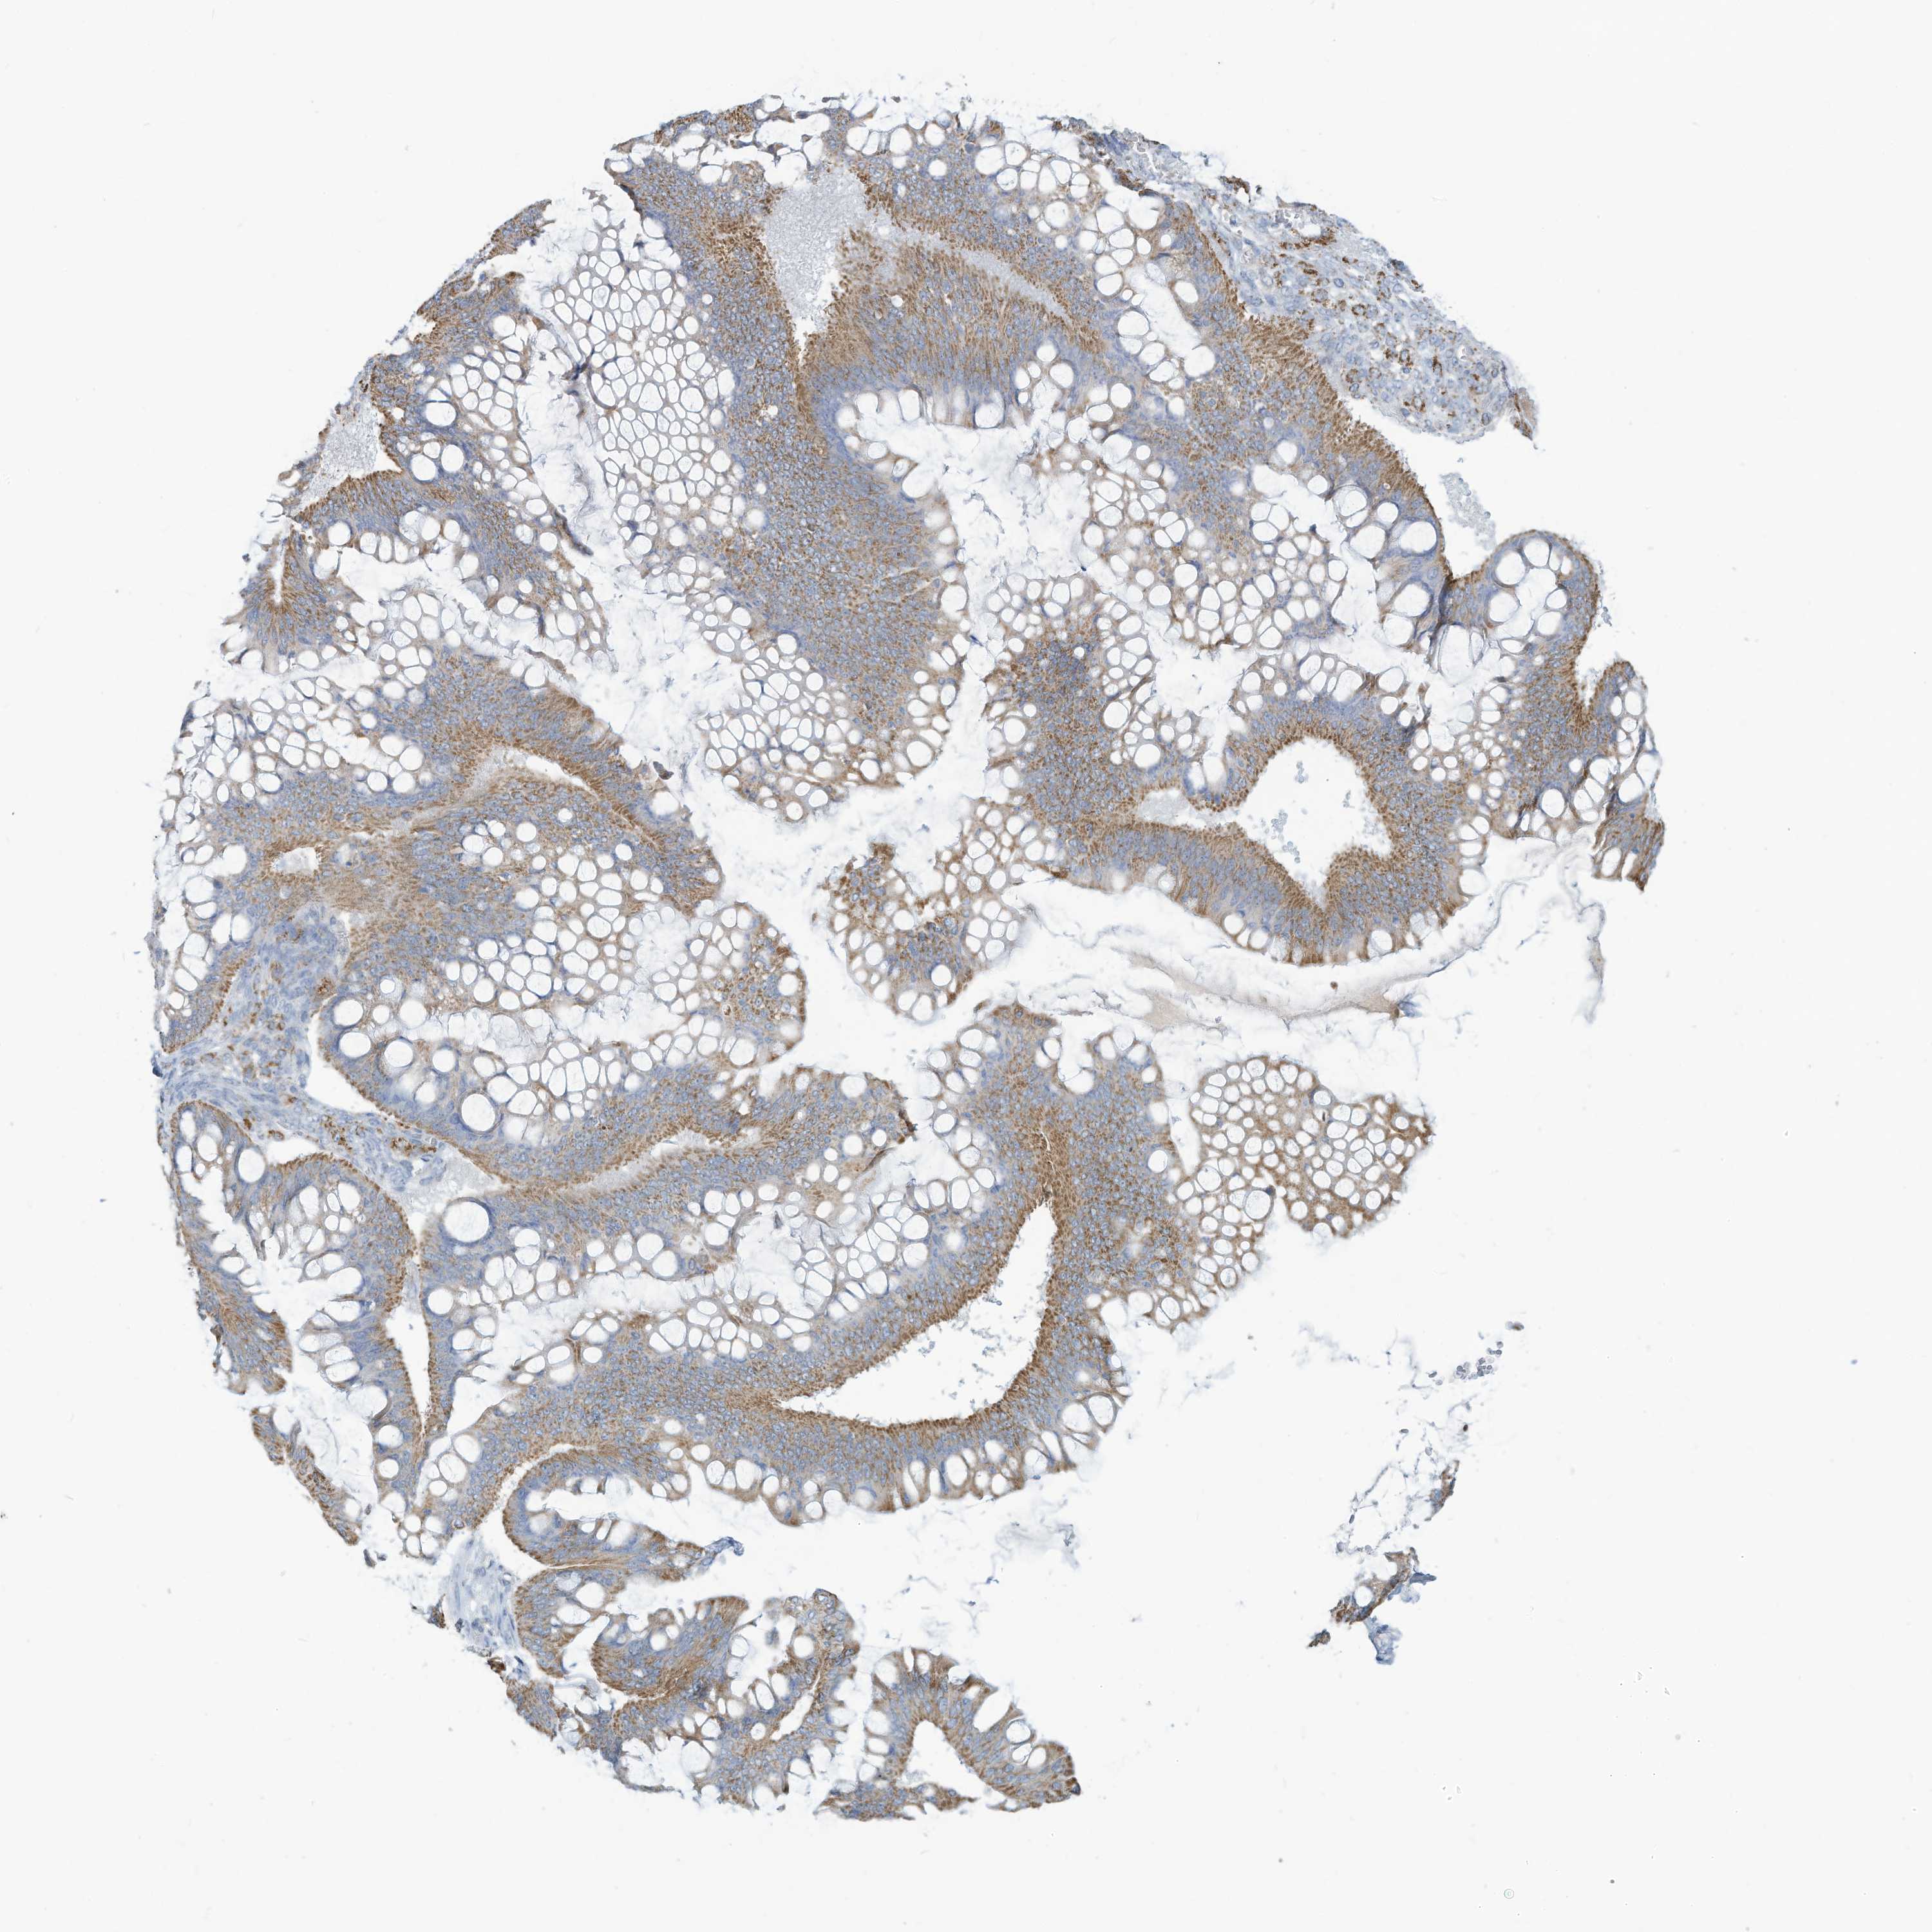

OVARIAN CANCER - Protein expressioni

A mouse-over function shows sample information and annotation data. Click on an image to view it in a full screen mode. Samples can be filtered based on level of antibody staining by selecting one or several of the following categories: high, medium, low and not detected. The assay and annotation is described here.

Note that samples used for immunohistochemistry by the Human Protein Atlas do not correspond to samples in the TCGA dataset.

Antibody stainingi

Antibody staining in the annotated cell types in the current human tissue is reported as not detected, low, medium, or high, based on conventional immunohistochemistry profiling in selected tissues. This score is based on the combination of the staining intensity and fraction of stained cells.

Each image is clickable and will lead to virtual microscopy that enables deeper exploration of all samples and also displays staining intensity scores, fraction scores and subcellular localization as well as patient and tissue information for each sample.

Antibody HPA031862

Staining

High

Medium

Low

Not detected

Intensity

Strong

Moderate

Weak

Negative

Quantity

>75%

75%-25%

<25%

None

Location

Nuclear

Cytoplasmic/membranous

Cytoplasmic/membranous,nuclear

Cystadenocarcinoma, mucinous, NOS